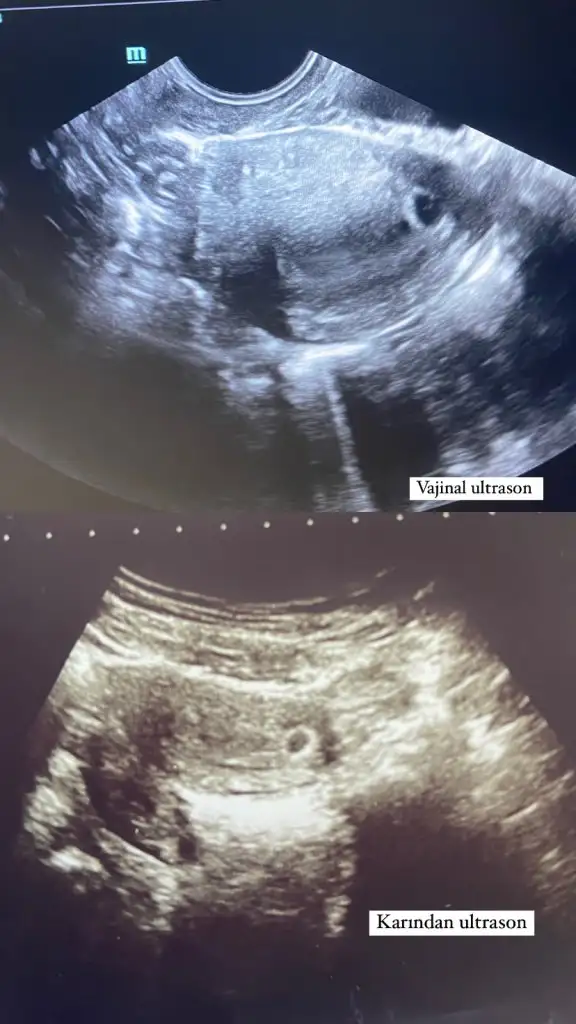

Kızlar transferin 20 gün sonra alttan vajinal muayene oldum kese göründü ve içinde 2 tane nokta vardı doktor bebekte içinde dedi internetten baktım yolk sac diye bir şey çıkıyor karşıma acaba 2 noktadan biri yolk sac diğeri bebek mi doktor ondan mı bebekte içinde dedi

Evet biri yolk biri bebek oluyor doktorum bana bu sekilde olan gebelik guzel ilerler demisti

Haftaya toplar o kendini 5 haftalikda kese kolay kolay gozukmez karından zaten yanlis ölçülmüş olabilir